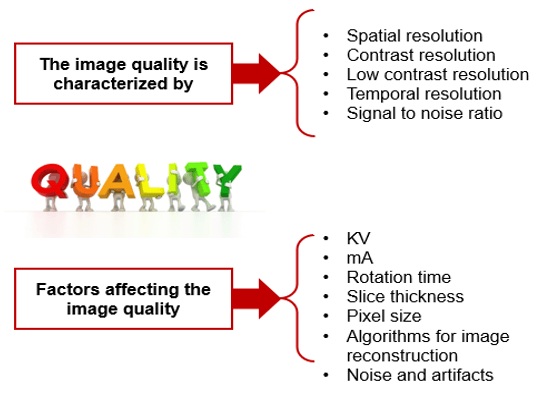

Essentially there are three main parameters, spatial resolution, contrast resolution and noise with many factors impacting quality.

Spatial Resolution

Many factors can impact image quality. Technical factors such as kVp and mA, slice thickness and rotation time, the pixel size and algorithms for the reconstruction and finally noise and artifacts.

Spatial resolution describes the amount of blurring in an image. Contrast resolution is the ability to differentiate small differences in density within the image. Spatial resolution in CT is the ability to distinguish between objects or structures that differ in density. A high spatial resolution is important for one to discriminate between structures that are located within small proximity to each other.

The number of line pairs per unit length is called the spatial frequency. Large objects have a low spatial frequency while small objects have a high spatial frequency.

- Standard resolution: 12 lines pairs/cm

- High resolution: 15 pl/cm

- Very high resolution: 30 pl/cm